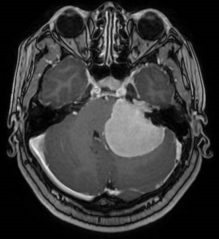

脑膜瘤术前核磁 术后CT